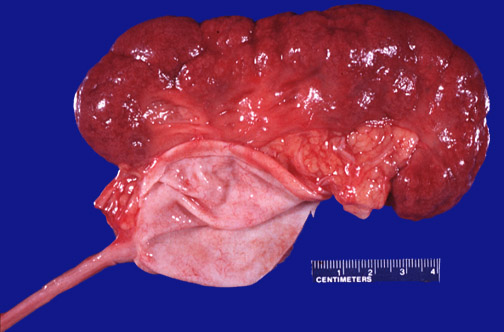

There is

scarring

of this kidney from chronic obstruction and pyelonephritis. The

renal pelvis

is markedly dilated, but the

ureter

is not, indicating that the point of obstruction is the

ureteropelvic junction

.